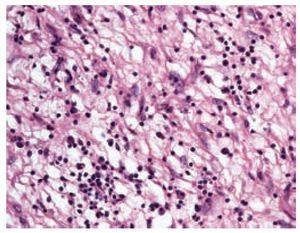

Paciente femenino de 51 años de edad, con diagnóstico de diabetes mellitus de varios años de evolución que inició su padecimiento un año previo al ingreso a nuestra institución con dolor epigástrico urente de moderada intensidad que remitía parcialmente a la administración de inhibidores de la bomba de protones. Un mes previo a su ingreso se agregó al cuadro anterior evacuaciones melénicas y en un estudio endoscópico se documentó tumoración gástrica, razón por la cual fue referida a nuestra institución. A su ingreso se documentó anemia microcítica hipocrómica con cifras de hemoglobina de 8.8 g/dL. Se le realizó una tomografía axial computada que reportó una lesión pediculada de centro hipodenso, dependiente del fondo gástrico con diámetro mayor de 7 cm (Figura 1). Una nueva evaluación endoscópica complementada con ultrasonido endoscópico, documentó una masa hipoecoica heterogénea de bordes discretamente irregulares de 5x8 cm dependiente de la capa muscular de la mucosa del cuerpo alto y fondo gástricos, respetando la muscular propia.

Figura 1. Tomografía axial computada que muestra la lesión pediculada de centro hipodenso dependiente del fondo gástrico.